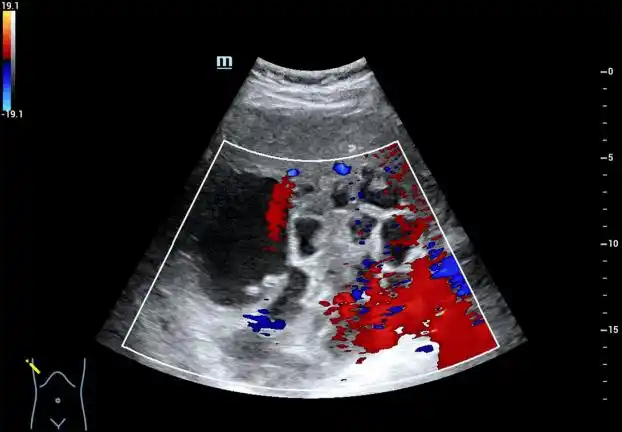

内可见粗大分隔,厚壁及壁结节图 1 2020 年 12 月肝脏超声提示脂肪肝

中重度脂肪肝